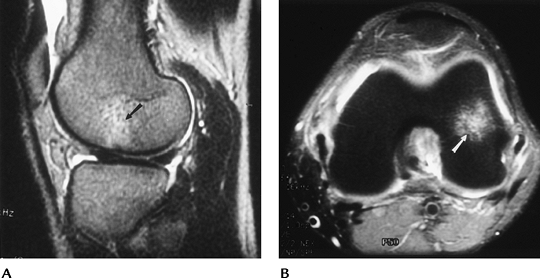

![]() |

FIGURE 5-56 AP (A), lateral (B), and notch views (C) demonstrating characteristic appearance and location of osteochondritis dissecans (arrow). Note the lesion is most easily appreciated on the notch view.

P.280

FIGURE 5-57

MR features of osteochondritis dissecans. Grade 1 = abnormal signal intensity, Grade 2 = linear defect in the cartilage, Grade 3 = abnormal signal intensity (↑ T2, ↓ T1-weighted image) around the fragment, Grade 4 = fragment has abnormal signal intensity surrounding it, and it may be loose. |